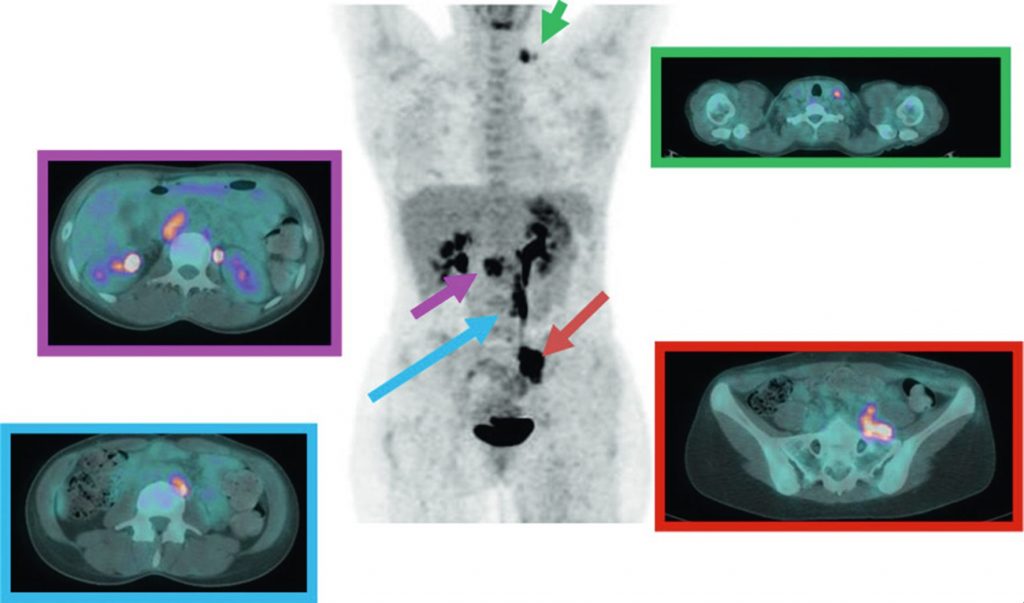

L’examen met en évidence des hyperfixations correspondant à des accumulations pathologiques de 18FDG en regard des atteintes lymphatiques et/ou métastatiques (figures 21.3 et 21.4).

Fig. 21.4 Bilan d’extension par TEP au 18FDG d’une récidive lymphatique iliaque commune gauche (rouge) dans un cancer du col utérin.

Découverte d’une atteinte lymphatique étagée : sus-claviculaire gauche (vert), cœliomésentérique droite (violet) et lombo-aortique latéro-aortique (bleu).

Source : CERF, CNEBMN, 2022.